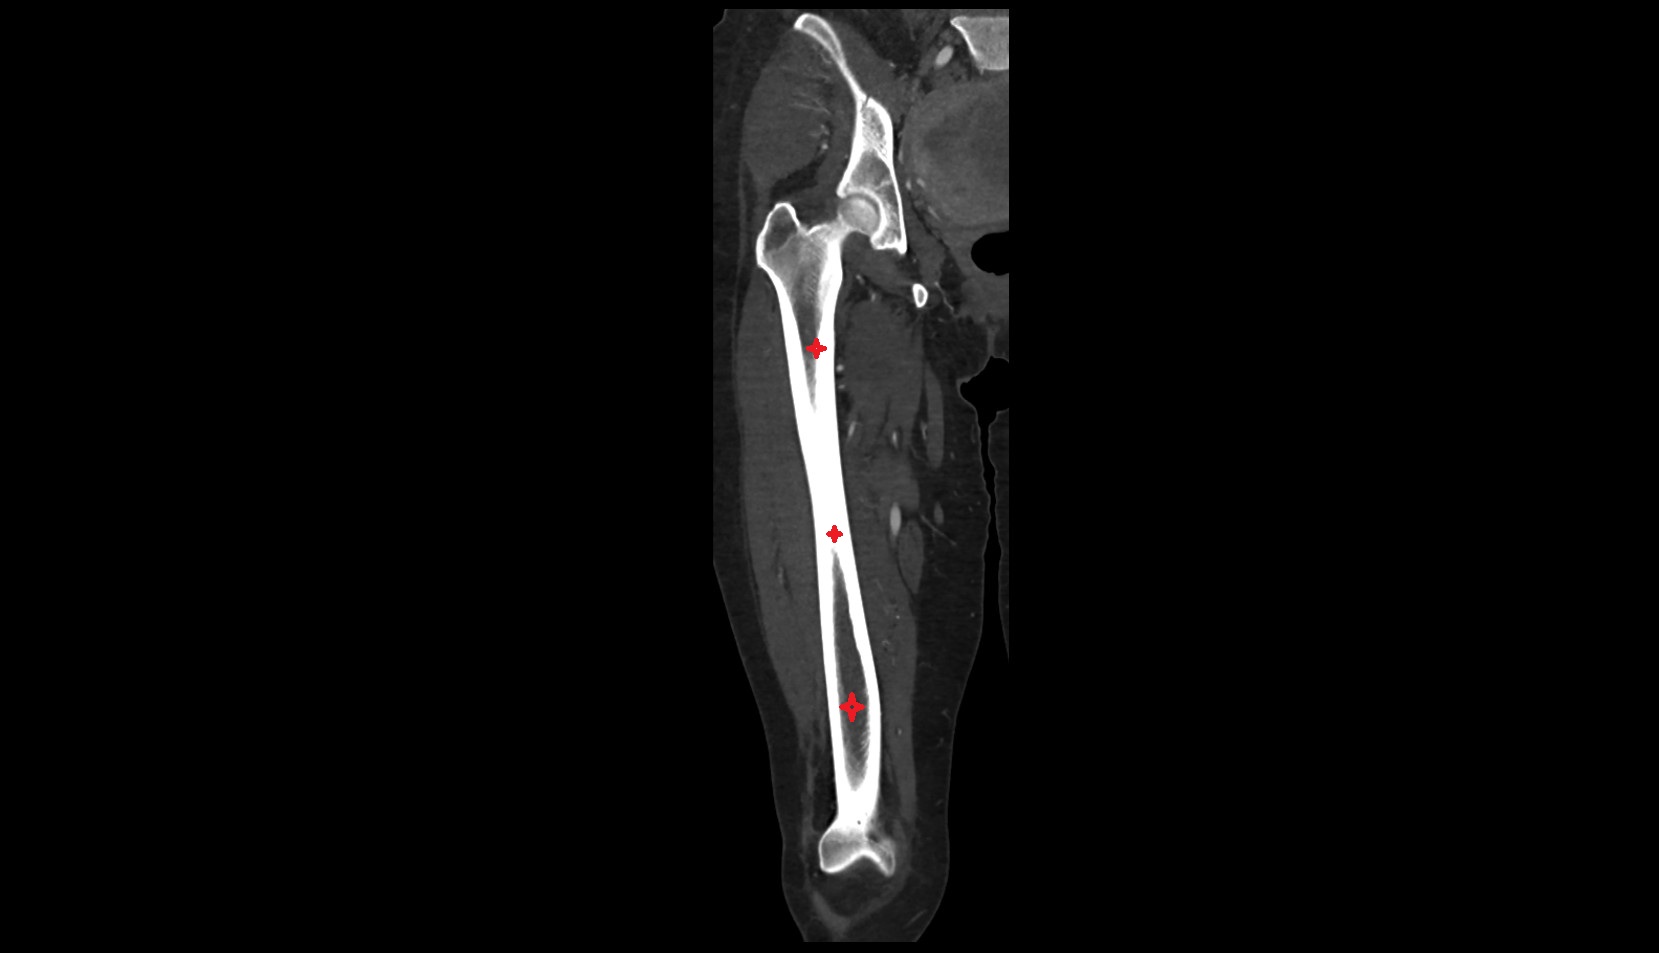

- Femur

- Femoral shaft

- Body of femur